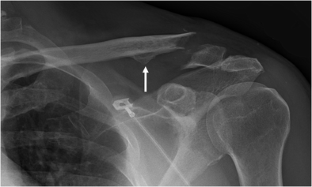

The most common of all clavicle injuries is a fracture, or break, of the bone in the middle third of the bone. Furthermore, risk factors for failure of conservative treatment have not been clearly defined. Musculoskeletal dysfunctions research paper. Soon after a fracture occurs, the body acts to protect the injured area, and forms a protective blood clot and callus around the fracture. 2 in contrast, accurate radiographic assessment of fractures of the medial third of the clavicle is difficult, and ct may be necessary for precise delineation of these fractures.